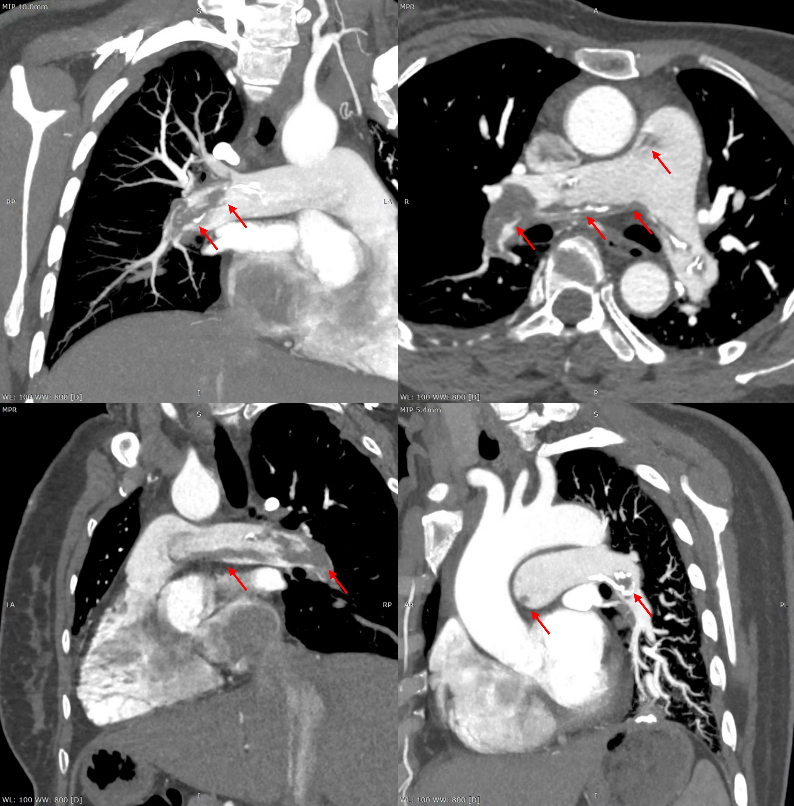

患者有5年高血压病史,3年前曾行子宫肌瘤切除术。已婚,孕2产1,已绝经。无特殊药物、外伤或疫区居住史,无吸烟饮酒习惯。入院查体:呼吸频率23次/min,血压111/73 mmHg,胸骨左缘第4肋间闻及2/6级收缩期吹风样杂音。实验室检查:D-Dimer 429 ng/mL(参考值0~243 ng/mL),B型利钠肽296 pg/mL(参考值0~100 pg/mL)。心电图提示窦性心律,SIQⅢTⅢ,V1-V4导联T波倒置(图 1)。超声心动图显示肺动脉及右心系统内多发囊性占位,右心轻度增大。入院后复查CTPA显示两肺段及段以上肺动脉多发充盈缺损(图 2)。入院诊断:肺动脉血栓栓塞症(中高危),右心系统占位(待查)。

| 图 2 肺动脉增强CT:两肺段及段以上肺动脉多发充盈缺损 |

患者接受抗凝治疗,D-Dimer水平下降,但症状无明显改善。D-Dimer数值与影像学所提示的栓塞负荷量不符,进一步诊断重点放在右心和肺动脉内的占位性病变上。是纤溶功能的异常?还是陈旧性血栓?患者多次凝血指标检查均在正常范围内;且病情呈现慢性起病、急性加重的特征,CTPA显示钙化及膨胀性生长的影像学表现,均与上述假设不符。影像学所提示的高栓塞负荷量需进一步解释,因此诊疗重点转向超声心动图所示的右心系统占位性病变。经胸基础超声心动图复查提示右心内存在多个等回声样团块,通过条索状回声相连,从右心房经过三尖瓣进入右心室,收缩期返回右心房。下腔静脉及髂静脉内均发现条索状回声,符合静脉内平滑肌瘤病(intravenous leiomyomatosis, IVL)诊断。结合患者3年前子宫肌瘤切除术病史及多次生育史,修正诊断为:IVL。患者接受手术治疗,病理分析确诊为IVL。术后恢复顺利出院,随访健康状况良好。本研究获得首都医科大学附属北京安贞医院伦理委员会批准(伦理审批号:2025094x),并已获得患者的知情同意。

2.2 超声心动图和CTPA的连续追踪为明确IVL诊断提供了重要的线索和依据通过心脏彩超发现右心系统异常肿物成为诊断转折点,”血栓”呈现明显延续性,结合子宫肌瘤切除术病史,成为拟诊IVL的重要线索。CTPA显示充盈缺损部位肺动脉呈扩张倾向,与血栓不符,弥漫钙化亦不能用”机化血栓”解释。